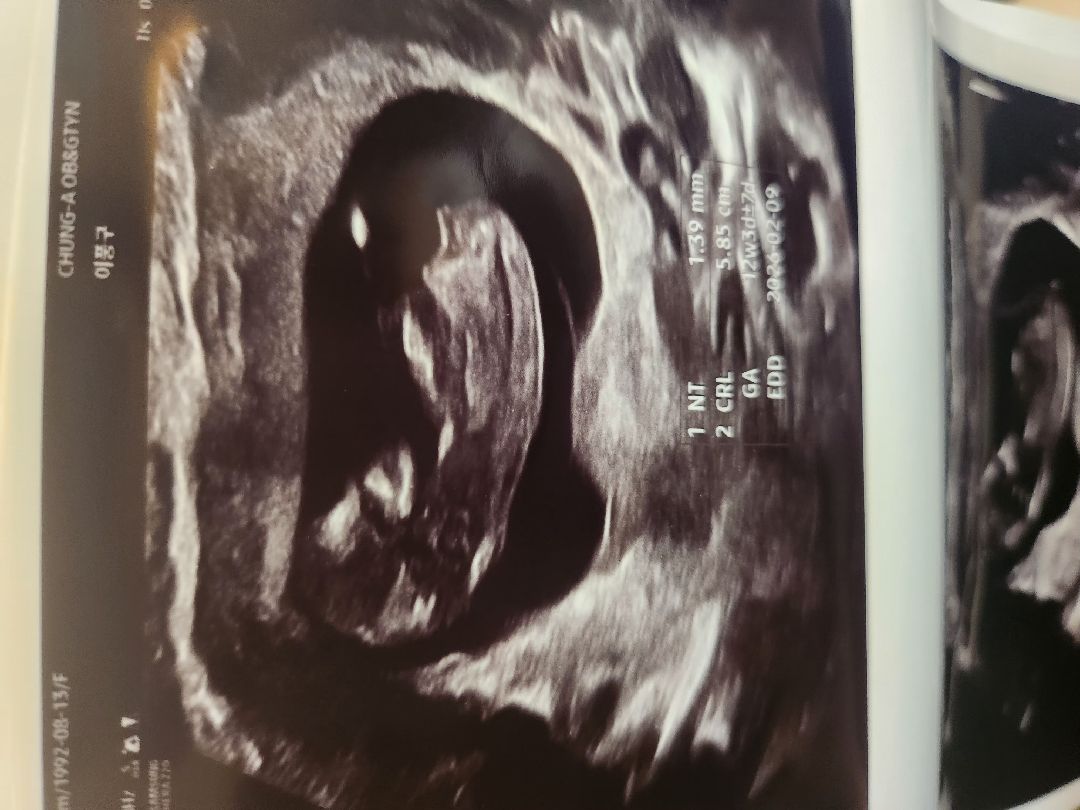

각도법 봐주세요

아들일까요 딸일까요ㅠ